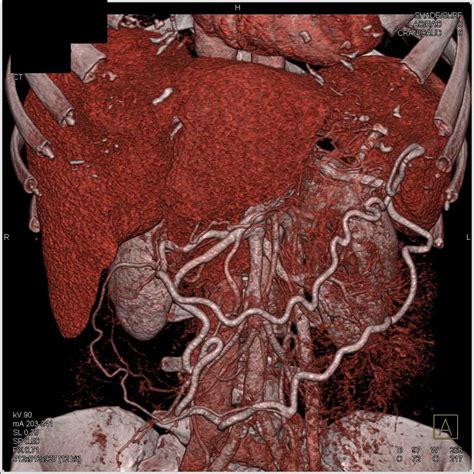

In addition to standard CT scans, advanced imaging techniques can provide even more detailed information about pancreatic adenocarcinoma. These techniques include:

• Magnetic Resonance Imaging (MRI): MRI uses magnetic fields and radio waves to create detailed images of the body. It can provide more information about soft tissues and is often used in conjunction with CT scans.

These advanced imaging techniques can complement the information provided by a Pancreatic Adenocarcinoma CT Scan, helping to create a comprehensive picture of the cancer's extent and characteristics.

• Surgery: Surgical removal of the tumor is often the first line of treatment for early-stage pancreatic adenocarcinoma. The type of surgery will depend on the location and size of the tumor.